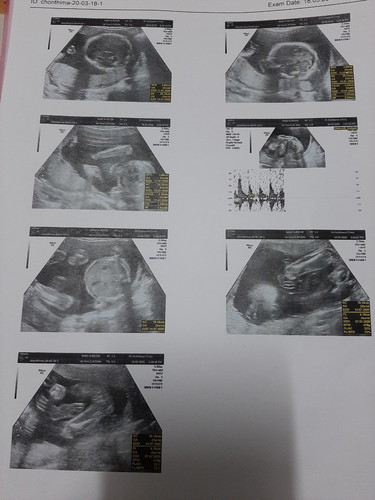

ดีใจมากค่ะ ได้ผู้หญิง ตรวจพบ46โครโมโซม ไม่พบความผิดปกติเชิงโครงสร้างและจำนวน ของทุกโครโมโซม ลุ้นแทบแย่อายุจะ38แล้ว โล่งอกไปคะ